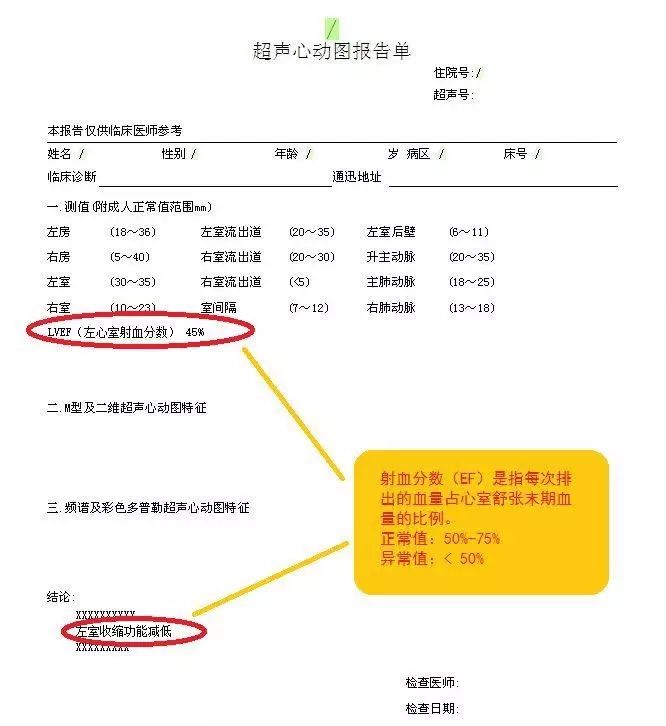

♥超声心动图:用来评估心脏的结构、功能状况。心超可以准确地反应心脏结构、搏动和血液流动的情况。您可以关注心超最主要的指标:LVEF(左心室射血分数),如果LVEF低于50%,一般视为心功能不全。

♥提示:如果通过上述检查确诊为心衰,那就需要积极配合医生进行治疗。千万不可掉以轻心或擅自用药。